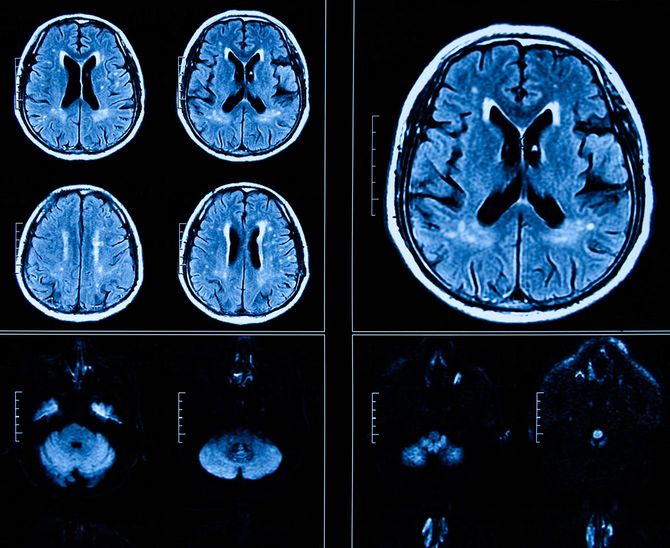

①前頭葉の萎縮……脳の前頭葉は、人間らしい「知性」――意欲・好奇心・創造性・計画性などを司る部分ですが、早い人で40代から縮み始める、つまり老化し始めます。萎縮が進むと、感情のコントロールがきかなくなったり思考が平板になったりします。

③動脈硬化……脳の血管は非常に細く、動脈硬化が進むと徐々に、細い血管の内部がつまりやすくなるため、とりわけ深刻です。脳の動脈硬化が進行すると自発性がなくなります。